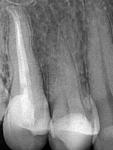

| Рис. 61 а-в Форма устьев корневых каналов 1.5 зуба: щечного и язычного, соответственно | ||